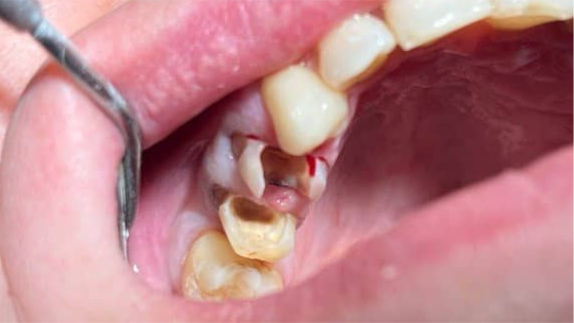

Сильное разрушение двух жевательных зубов:

как циркониевые коронки устранили травму слизистой и вернули возможность нормально жевать

После

Осложнения, возникшие из‑за длительного отсутствия лечения

1. Хроническая травма слизистой — острые края разрушенных зубов постоянно контактировали со щекой, вызывая болезненные эрозии, что повышало риск инфицирования мягких тканей.

2. Функциональная перегрузка противоположной стороны — жевание только на здоровой стороне привело к стираемости зубов-антагонистов и повышенной нагрузке на височно-нижнечелюстной сустав.

3. Прогрессирующее разрушение — с каждым месяцем зубы продолжали крошиться, приближаясь к уровню десны, что усложняло последующее восстановление.

Результат лечения

Пациенту предложен и реализован следующий план лечения:

Этап 1. Подготовка зубов

• Выполнено качественное перелечивание каналов.

• Создана культевая внутриканальная вкладка из стекловолокна для усиления опоры под коронку.

Этап 2. Препарирование (обточка) зубов

• Устранены острые травмирующие края.

• Зубам придана правильная форма культи с учётом толщины будущих коронок.

• Все манипуляции проведены под местной анестезией — пациент не испытывал боли.

Этап 3. Изготовление и фиксация циркониевых коронок

• Сняты слепки, изготовлены две индивидуальные коронки из диоксида циркония в зуботехнической лаборатории.

• Коронки зафиксированы на подготовленные зубы с использованием адгезивного цемента двойного отверждения.

По завершении лечения пациент получил:

• устранение травмы щеки и слизистой — острые края полностью покрыты гладкими коронками;

• восстановление жевательной функции — возможность пережёвывать любую пищу без боли и ограничений;

• сохранение собственных зубов — удаления удалось избежать;

• комфорт в повседневной жизни — пациент перестал избегать нагрузки на протезированную сторону;

• долгосрочный прогноз — при правильном уходе коронки прослужат 10–15 лет и более.

Пациент отметил, что впервые за несколько лет может спокойно есть мясо, овощи и даже твёрдые фрукты (яблоки, груши), не опасаясь боли или новой травмы щеки.